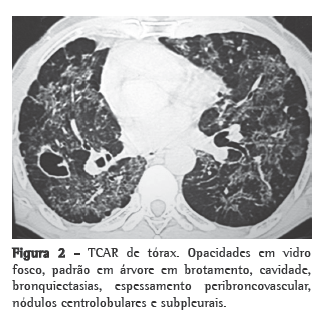

Na TCAR (Figura 2), podem ser visualizados nódulos, opacidades em vidro fosco, aspecto em árvore em brotamento, lesões acinares, bandas parenquimatosas, espessamento do interstício peribroncovascular, cavidades, reticulosidades, sinal do "halo invertido", enfisema paracicatricial e bronquiectasias de tração.(8,9)